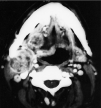

Fig. 1. Tomografía computarizada cervical en la que se observan adenopatías cervicales derechas y una masa heterogénea en paladar blando del mismo lado.